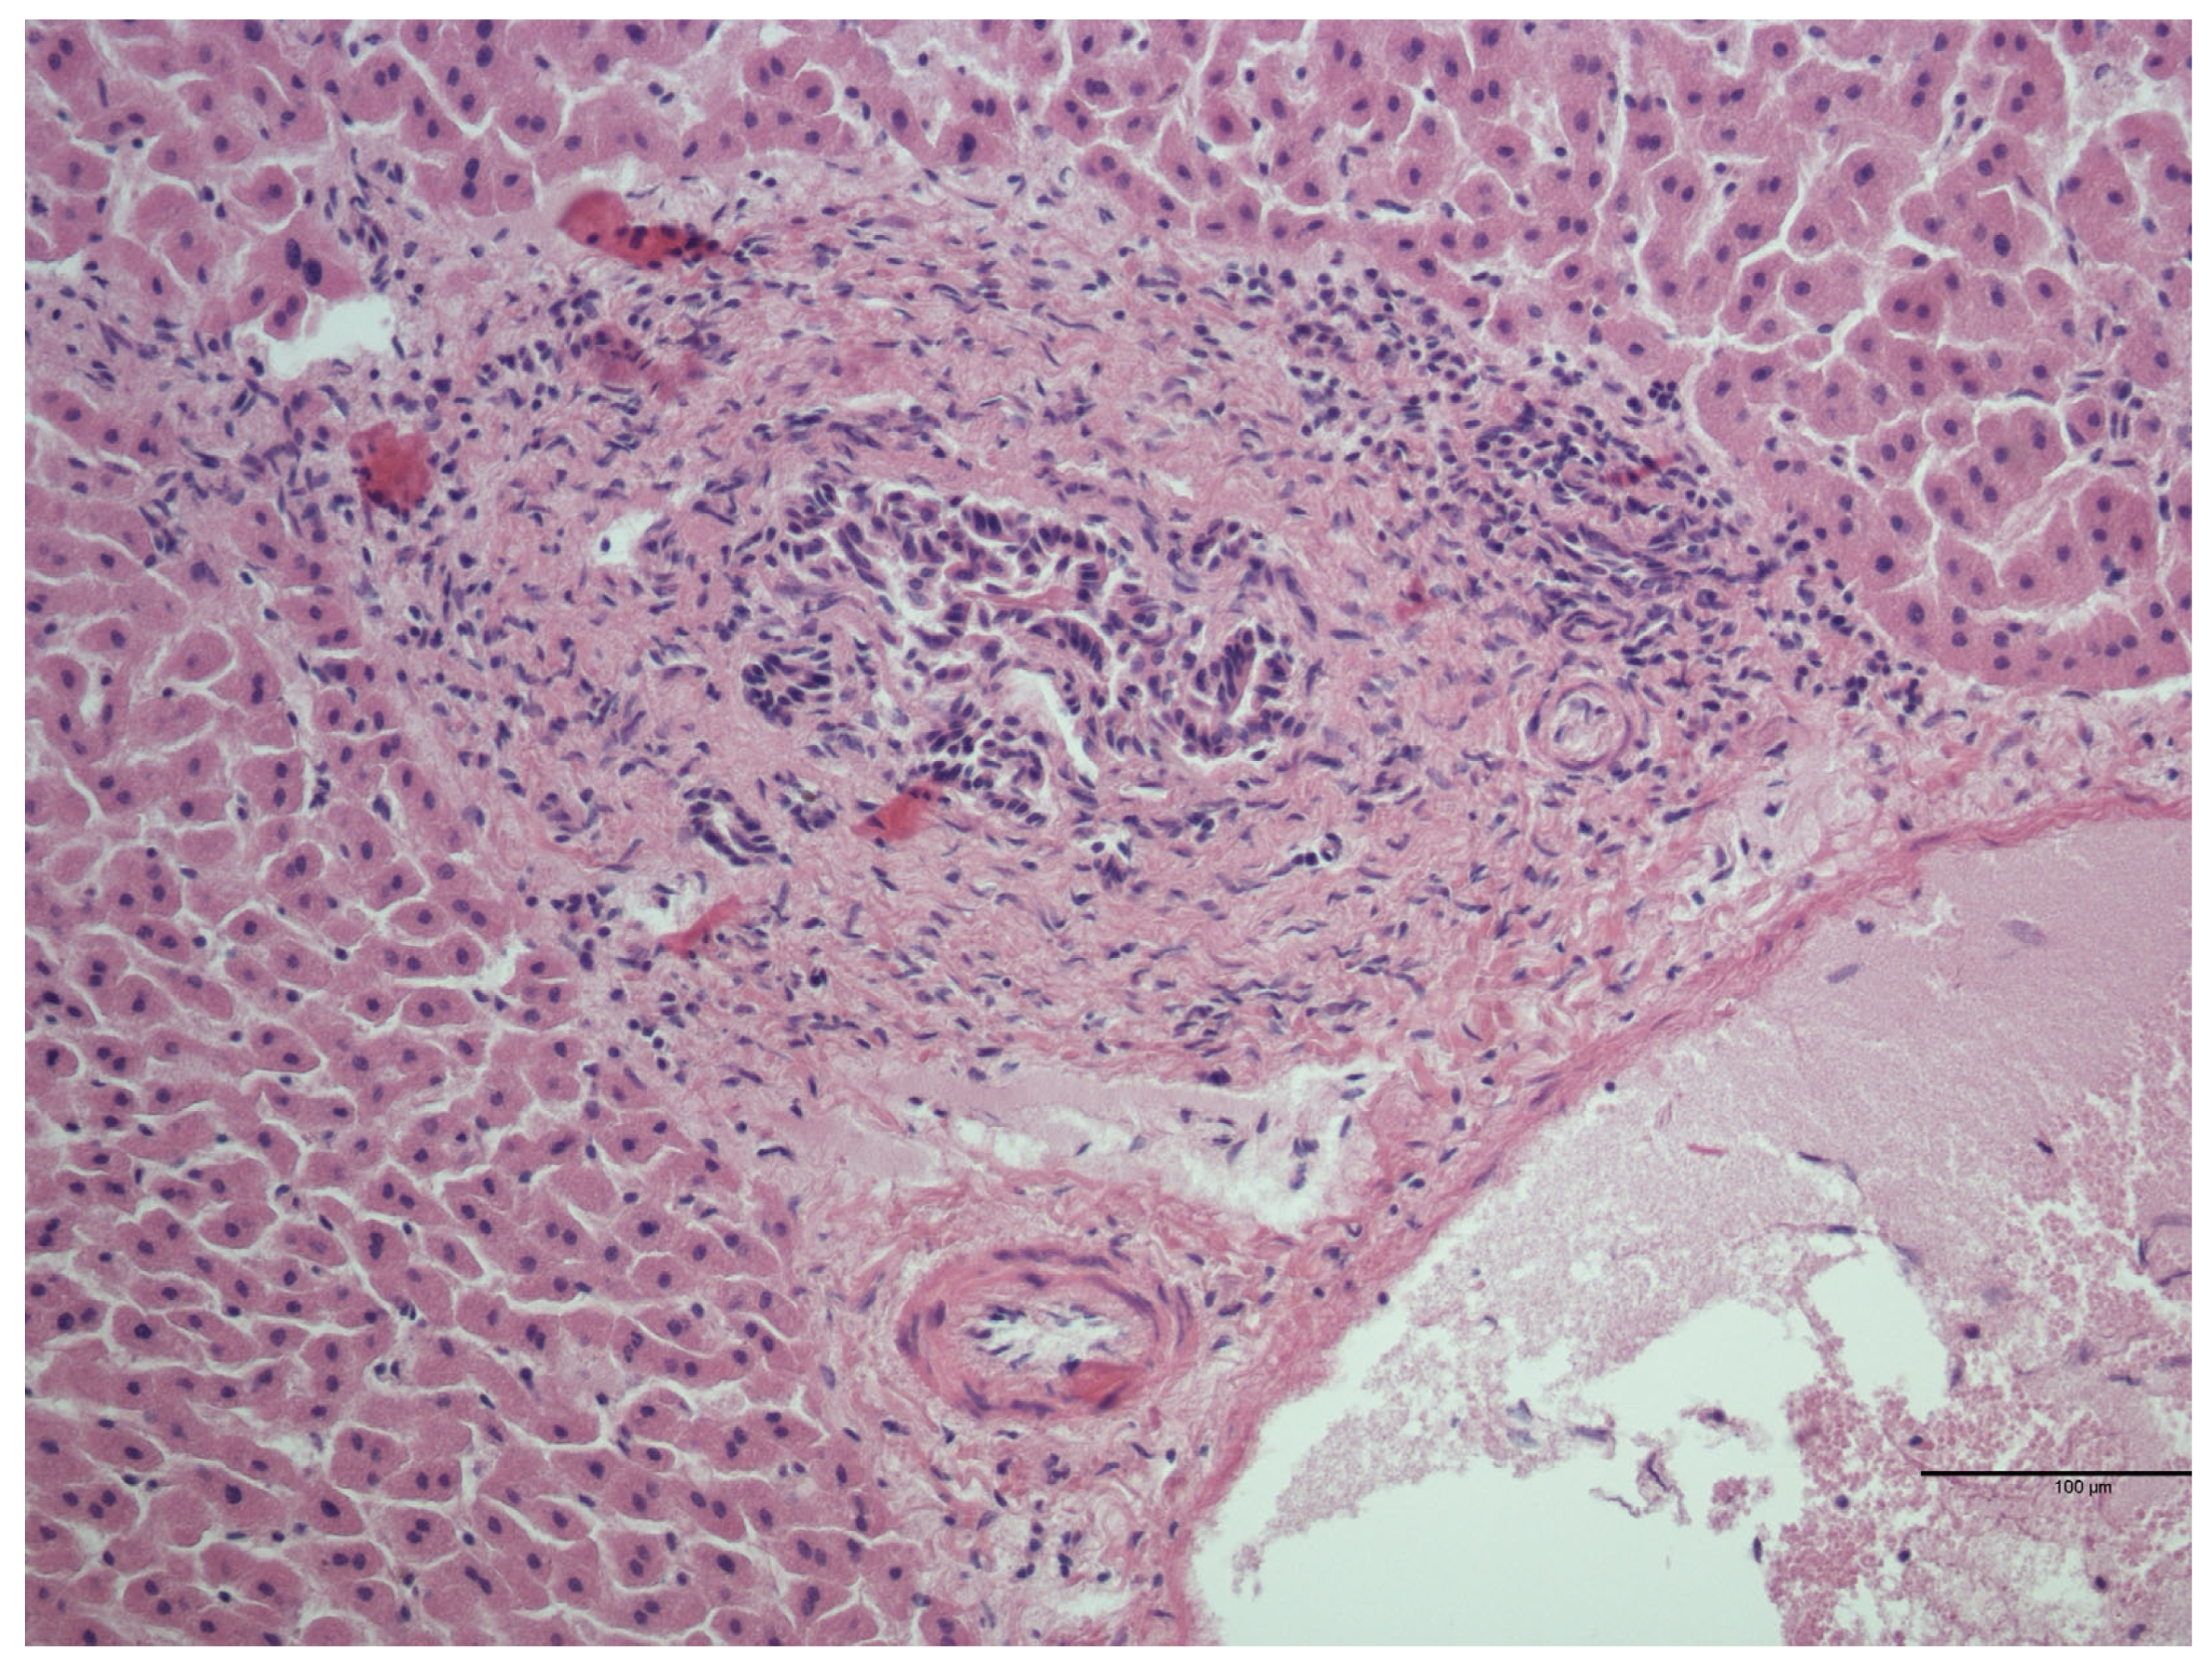

| Lesion | Number of Samples Positive for the Lesion/Total Number of Microscopical Lesions (%) |

|---|---|

| Interstitial lymphocytic nephritis | 20/23 (87.0%) |

| Urine crystals | 2/23 (8.7%) |

| Perivascular lymphocytic infiltrate | 1/23 (4.3%) |

| Cyst with focal lymphocytic infiltrate | 1/23 (4.3%) |

| Interstitial lymphocytic and eosinophilic nephritis | 1/23 (4.3%) |

| Lymphocytic infiltrate into perirenal fat | 1/23 (4.3%) |